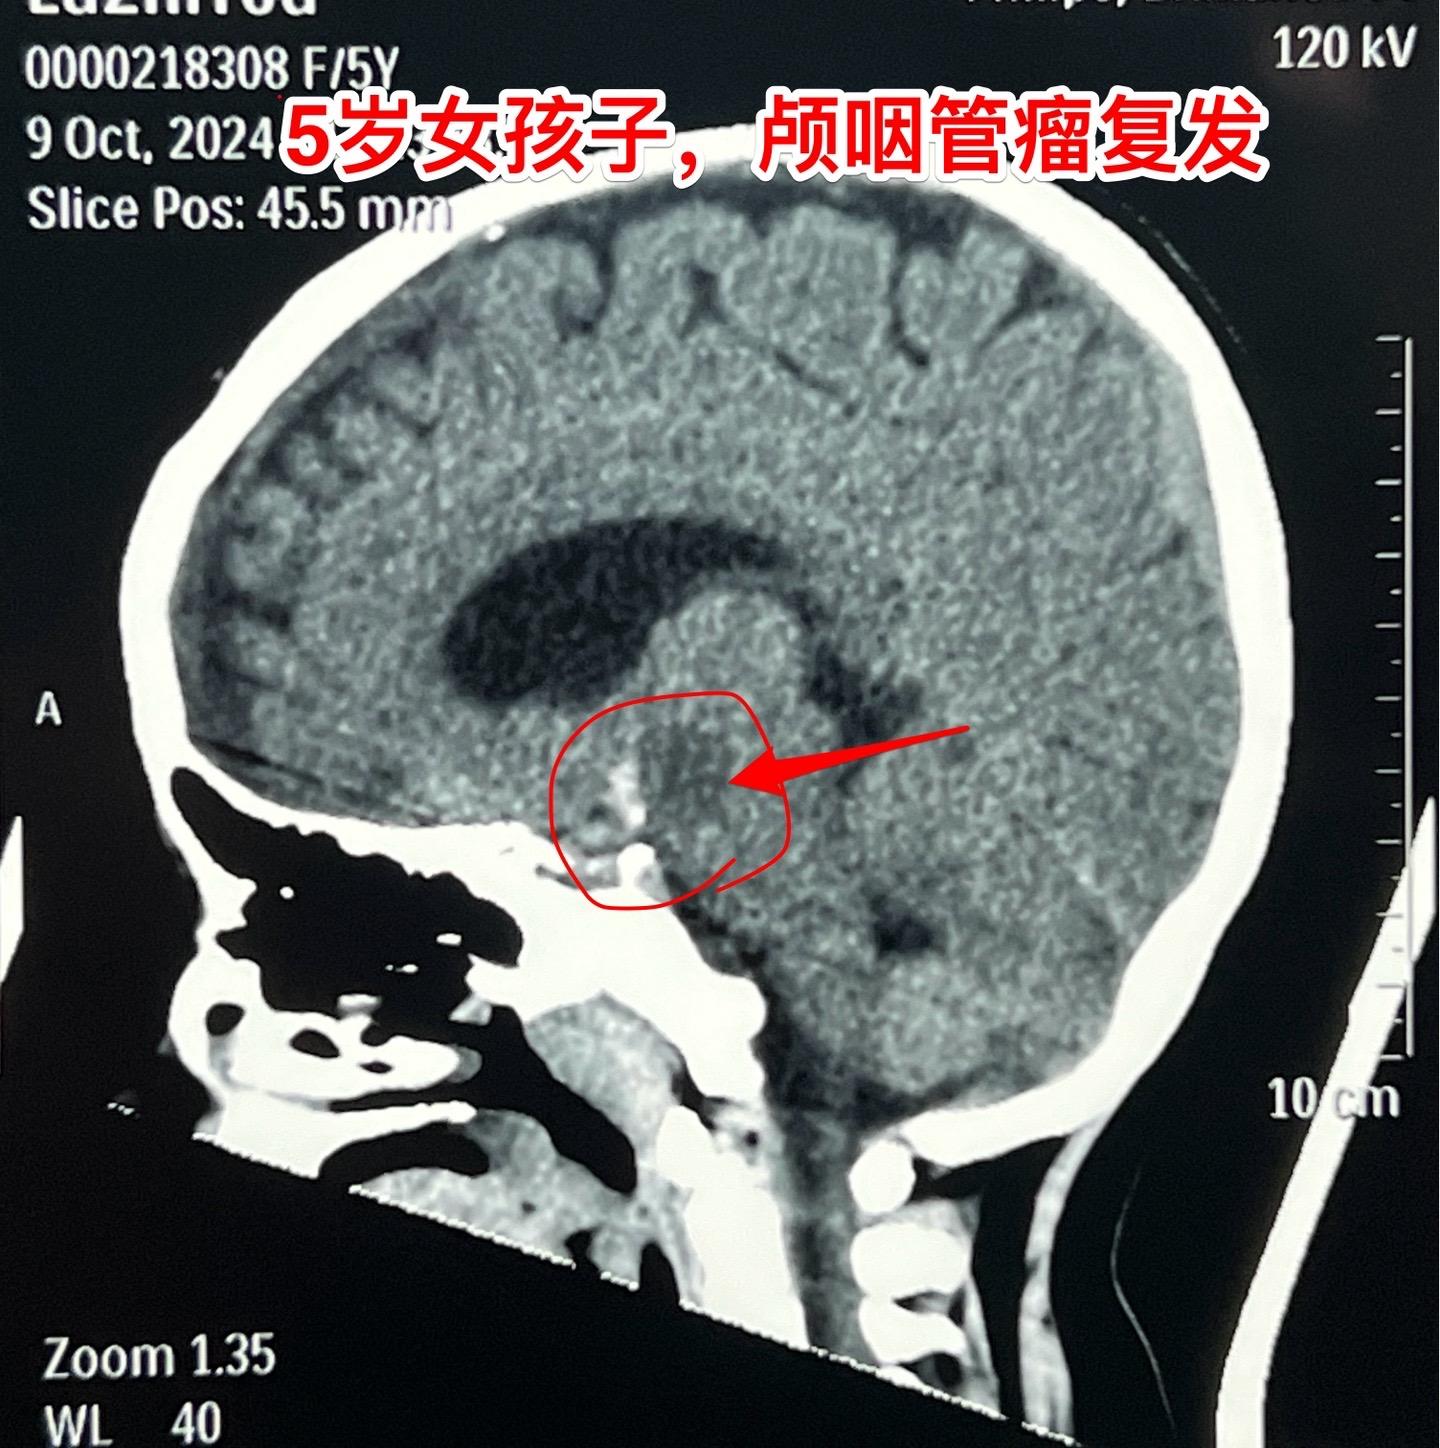

复发颅咽管瘤的手术难度好判断吗?5岁广州的女孩子,颅咽管瘤复发了。第一...